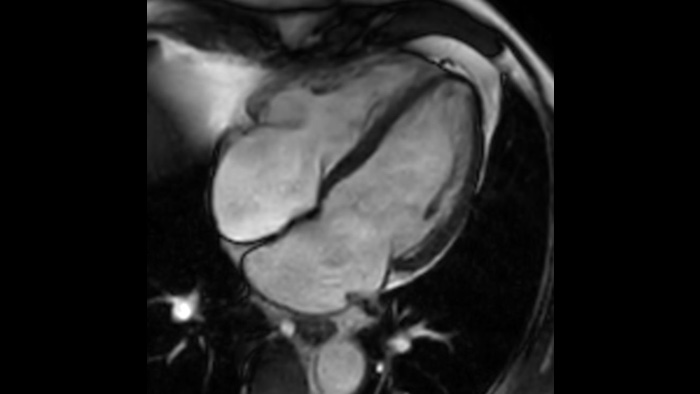

There are lots of applications that can improve the workflow. Like Compressed SENSE, VitalEye and VitalScreen. We feel that this system combines both safety and improved workflow.

Speed & Comfort Provide up to 40% reduction in breath holds, with virtually equal image quality4.

This innovative solution offers many clinical, operational and financial benefits.